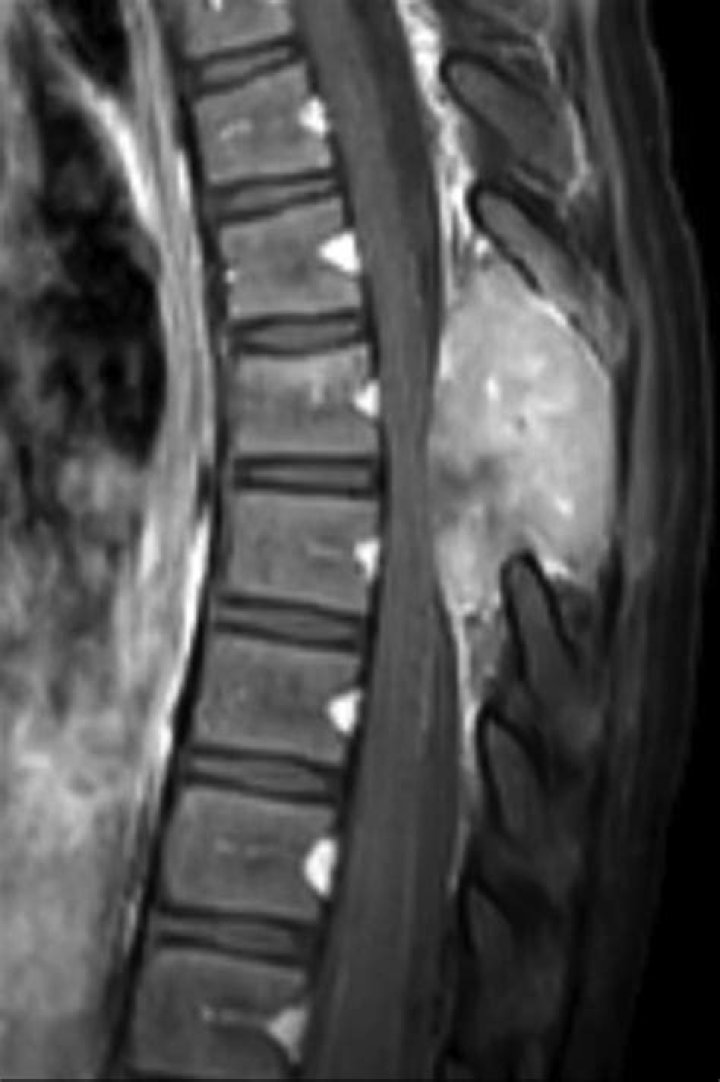

Can spinal tumor be seen on xray?

Spine X-rays provide detailed images of the bones of the spine, and can be taken separately for the three main parts of the spine. Conditions that may show up in spine x-rays include fractures, tumors and arthritis.

Can CT scan detect spinal tumor?

A CT scan is only rarely used to help diagnose spinal tumors. Biopsy. The only way to determine the exact type of a spinal tumor is to examine a small tissue sample (biopsy) under a microscope. The biopsy results will help determine treatment options.

How do you detect chordoma?

How is a chordoma diagnosed? Sometimes, especially at the base of the spine, a lump will be found. In other cases, lesions show up on computed tomography (CT) and magnetic resonance imaging (MRI) scans. A biopsy will be done to diagnose a chordoma and to differentiate it from other types of tumors.